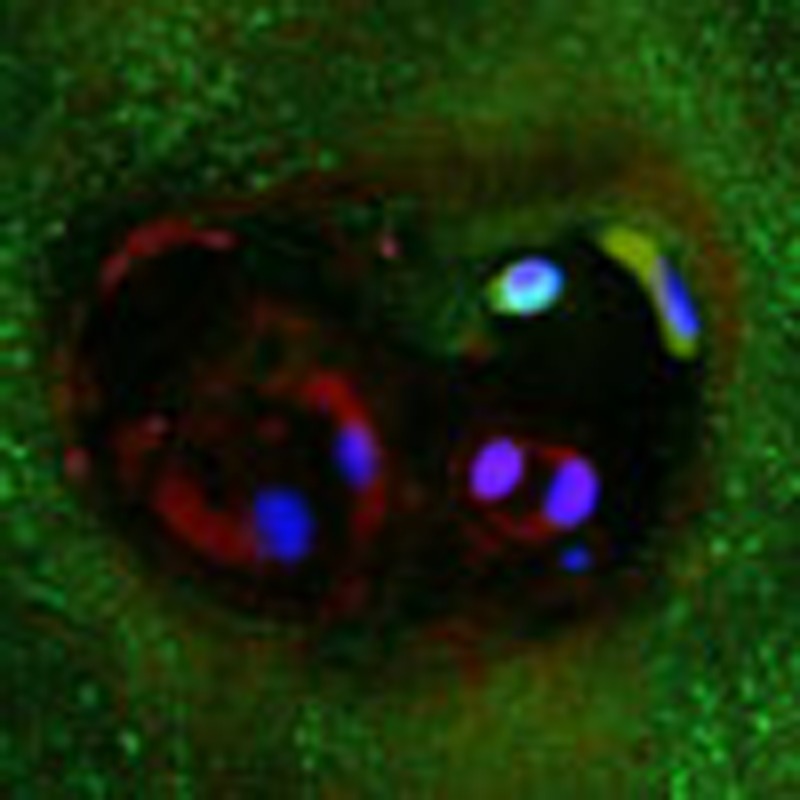

Figure 5. Expression of Tie2 and GD2 in IVD tissues.

(a) Histological analysis of paraffin sections of 9-week-old mouse tail IVDs sectioned in the mid-coronal plane and stained with haematoxylin and eosin (HE, top left). Line A indicates the direction of the sectioning, and the location was identified in the frozen sections used for immunofluorescence. The HE image on the far left shows the AF and NP border, and the right HE image shows the central NP. Fluorescent staining results show visualization of F-actin fibres of the cytoskeleton of mNP cells by phalloidin reagent (green). Expression of Tie2 (top middle, red in mNP cells; top right, the stained cells magnified) and GD2 (bottom middle, red in mNP cells; bottom right, stained cells magnified) on the cell surface was confirmed. Yellow scale bars, 20 μm; black and white bars, 50 μm. (b) Histological paraffin section of human IVD tissue (Thompson grade II) stained with HE identifies the corresponding locations in the following frozen sections indicated in the middle and lower panels (top panel; scale bar, 1 mm). Middle (HE) and bottom (immunofluorescence) panels of sections obtained from the AF (far left) to central NP (far right). No apparent immunostaining was detected for Tie2 or GD2 in the AF area (bottom left), but GD2+ and Tie2+ cells were detected (bottom centre to far right) in other areas. Scale bars, 50 μm. DAPI, 4′,6-diamidino-2-phenylindole.